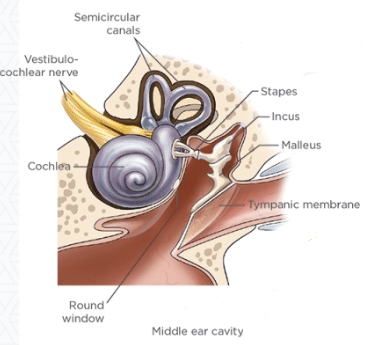

• middle ear

There

are two middle ears, the right one and the left one, each of which

consists of the ear drum, an air-filled

tympanic cavity, and three small bones (ossicles)

labelled the malleus, incus, and stapes, along with

their muscles and ligaments, and the tympanic membrane (eardrum).

(See the diagram at right.)

There

are two middle ears, the right one and the left one, each of which

consists of the ear drum, an air-filled

tympanic cavity, and three small bones (ossicles)

labelled the malleus, incus, and stapes, along with

their muscles and ligaments, and the tympanic membrane (eardrum).

(See the diagram at right.)

In an April 2024 article, UK researchers examined the structure and scaling of the middle ears of 17 dog breeds, including a cavalier King Charles spaniel. They found that the cavalier "stood out the most" with larger volumes of the ossicular bones (and also larger labyrinth volume) than any other breed. They suggested that these differences may be related to PSOM in the breed.